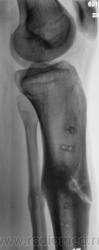

Щелевидный дефект до 1/2 d кости обусловлен, по всей вероятности, необезыствленной остеоидной тканью. Со временем "захряснет". Клиницисты в таких случаях констатируют консолидированный перелом.

СОСТОЯНИЕ КОСТНЫХ ОТЛОМКОВ УДОВЛЕТВОРИТЕЛЬНОЕ. ЛИНИЯ ПЕРЕЛОМА НЕ ОПРЕДЕЛЯЕТСЯ. ИЗБЫТОЧНАЯ КОСТНАЯ МАЗОЛЬ. А ДЛЯ ЧЕГО МСЭК?

Пациент борется "за группу" применяя все тактические дозволенные и не дозволенные действия. На мой взгляд , некоторая избыточная костная мозоль есть. Длинник кости сохранен.

Консолидированный  перелом костей голени на границе верхней и средней 1\3 диафизов. Состояние костных отломков удовлетворительное. Линия перелома, практически, не визуализируется. В б\б кости линия простветления до 1\2 поперечника, обусловленная дефектом костной ткан. Определяется избыточная костная мозоль. В верхней и средней 1\3 дефекты костной ткани как следствие перенесенной операции МОС. А на основании чего этот упорный пациент надеется получить группу?!  Все сопоставлено, срослось...  ???

Линия перелома хорошо видна на боковом снимке

Видна линия «просветения», в которой содержание солей кальция понижено. Но она не является линией перелома и пересекает не весь поперечник утолщенного диафиза. Главное: опорная функция восстановлена?